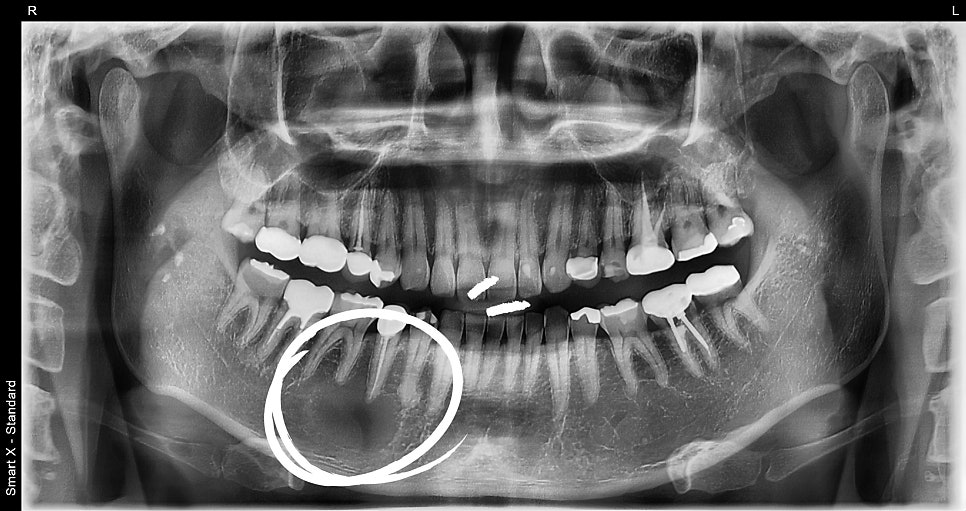

As a result of panoramic imaging and CBCT (3D CT) examination,

a well-defined radiolucent lesion was identified within the mandible in that area.

Diagnostic result: suspected benign tumor-like lesion within the mandible. The lesion was a circular cystic lesion about 2.5 cm in size, and unlike inflammation, it was a well-demarcated lesion distinguishable from the surrounding tissue.

Differential diagnosis: possibility of periapical cyst / cementoblastoma / odontogenic tumor, etc.

Comparison before and after treatment

📸 Before surgery

– Cystic lesion at the periapical area